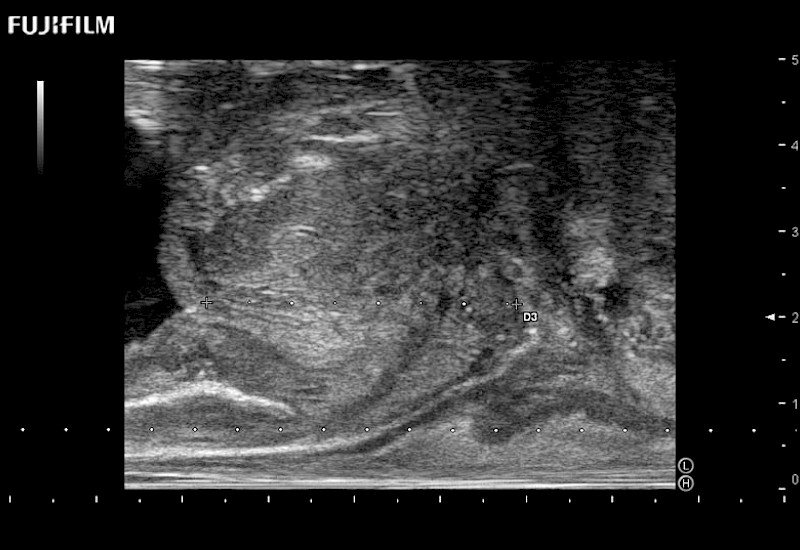

Ideal transducer for Transperineal Biopsy, Hydrogel Spacer Placement, Brachy LDR & HDR, Cryo, and MPMRI procedures.